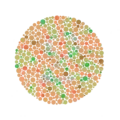

Il permet de détecter toutes les déficiences dichromatiques sauf la tritanopie et la tritanomalie, d’ailleurs très rare. Une planche pseudo-isochromatique est constituée d’une mosaïque de points de couleurs différentes, disposés de façon apparemment aléatoire, au sein duquel apparaît une forme sur un fond. En réalité, les couleurs utilisées sont situées sur des axes de confusion colorés prédéterminés pour mettre en évidence un type de daltonisme précis. On utilise un nombre réduit de teintes. Chacune d’elles apparaît à plusieurs degrés de taille, de saturation et de luminosité. Ces degrés sont identiques pour chacune des couleurs représentées. Un ensemble de points reproduit une forme reconnaissable par l’unité de la teinte, mais, au sein de cette forme, on trouvera plusieurs saturations ou luminosités différentes de façon aléatoire. Le daltonien qui ne verra pas la couleur ne pourra pas non plus déchiffrer la forme par le seul fait d’une homogénéité de saturation ou de luminosité. À l’inverse, il existe des planches dans lesquelles cette homogénéité est utilisée pour faire percevoir des formes à des dichromates alors que les sujets normaux, trompés par des couleurs qui leur paraissent différentes, ne les percevront pas. Dans le daltonisme héréditaire, les lignes de confusion sont nettes et parfaitement déterminées. Cela permet une excellente fiabilité aux planches bien conçues, à la condition que les couleurs soient reproduites à l’impression. En revanche, par construction, une planche pseudo-isochromatique n’est pas adaptable et si l’axe de confusion du dichromate n’est pas rigoureusement celui qui a été prédéterminé, la planche sera jugée défectueuse. Cela se produit le plus souvent dans le cas d’une dyschromatopsie acquise. Chaque groupe de planches (tables) reproduites dans l’annexe (page 27 à 33) doit être interprété différemment.

- Les planches 2 à 5 se servent donc de la même confusion de couleurs. Normalement, des chiffres différents de ceux perçus par les sujets normaux sont visibles en cas de dichromie rouge vert. Le taux d’erreur de perception des chiffres différents, pour les daltoniens, est fluctuant.

- Les planches 6 à 9 sont de même valeur et explorent une confusion entre le rouge et le vert, très voisine de celle testée pour le groupe précédent mais possédant un fond différent. Les sujets anormaux perçoivent donc des chiffres autres.

Exemples de planches représentant successivement les numéros 12, 6, 2 (visible seulement en cas de déficience rouge-vert) et 42.

Ishihara Planche no 11. Ishihara Planche no 19.

Ishihara Planche no 19. Ishihara Planche no 23.